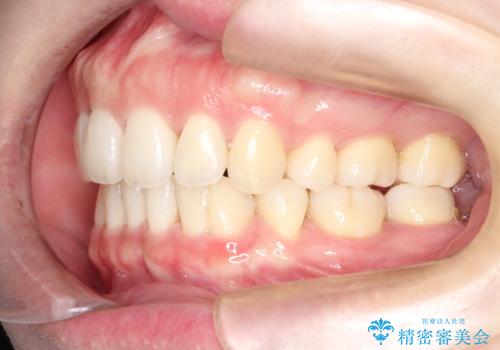

- 前歯の前突を主訴に来院されました。

下の前歯は癒合歯がある珍しいケースです。

治療に関しては小臼歯を4本抜歯して前歯を下げるような計画を立てて治療しました。